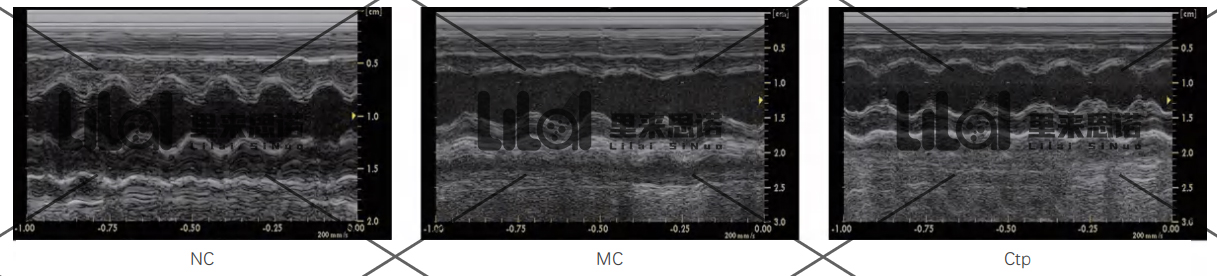

SPF級(jí)SD大鼠180~220 g,雄性。將大鼠隨機(jī)分為空白對(duì)照組(NC)、模型組(MC)、陽(yáng)性對(duì)照組(Captopril, Ctp)。

心功能檢測(cè):實(shí)驗(yàn)結(jié)束后進(jìn)行心臟超聲,檢測(cè)各組大鼠的心功能。結(jié)果發(fā)現(xiàn):與NC組相比,MC組大鼠左室射血分?jǐn)?shù)(LVEF)和左室短軸縮短率

(LVFS)顯著降低;而Ctp能顯著提高心衰大鼠LVEF和LVFS,改善心衰大鼠心功能(p<0.01)。